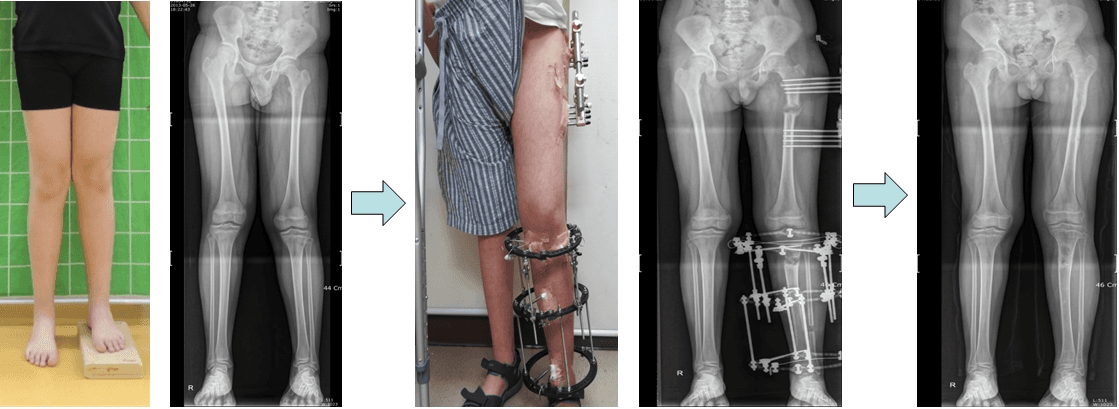

One leg had both the femur and tibia shorter, and both parts were lengthened simultaneously.

Both femur and tibia in one leg were shorter than the other. Both were lengthened at the same time.